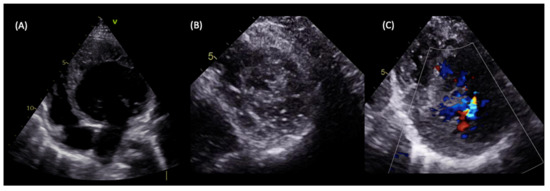

Figure 4.

LVNC in a 5-year-old patient with a family history of dilated cardiomyopathy presenting with heart failure symptoms. Transthoracic echocardiography showed dilated LV with severely impaired systolic function and an estimated ejection fraction of 30% (A), the spongy aspect of the apex on echocardiographic short axis view (B), and perfused intertrabecular recesses seen on a Colour Doppler (C), which are compatible with LVNC diagnosis according to both the Jenni and Stöllberger criteria.